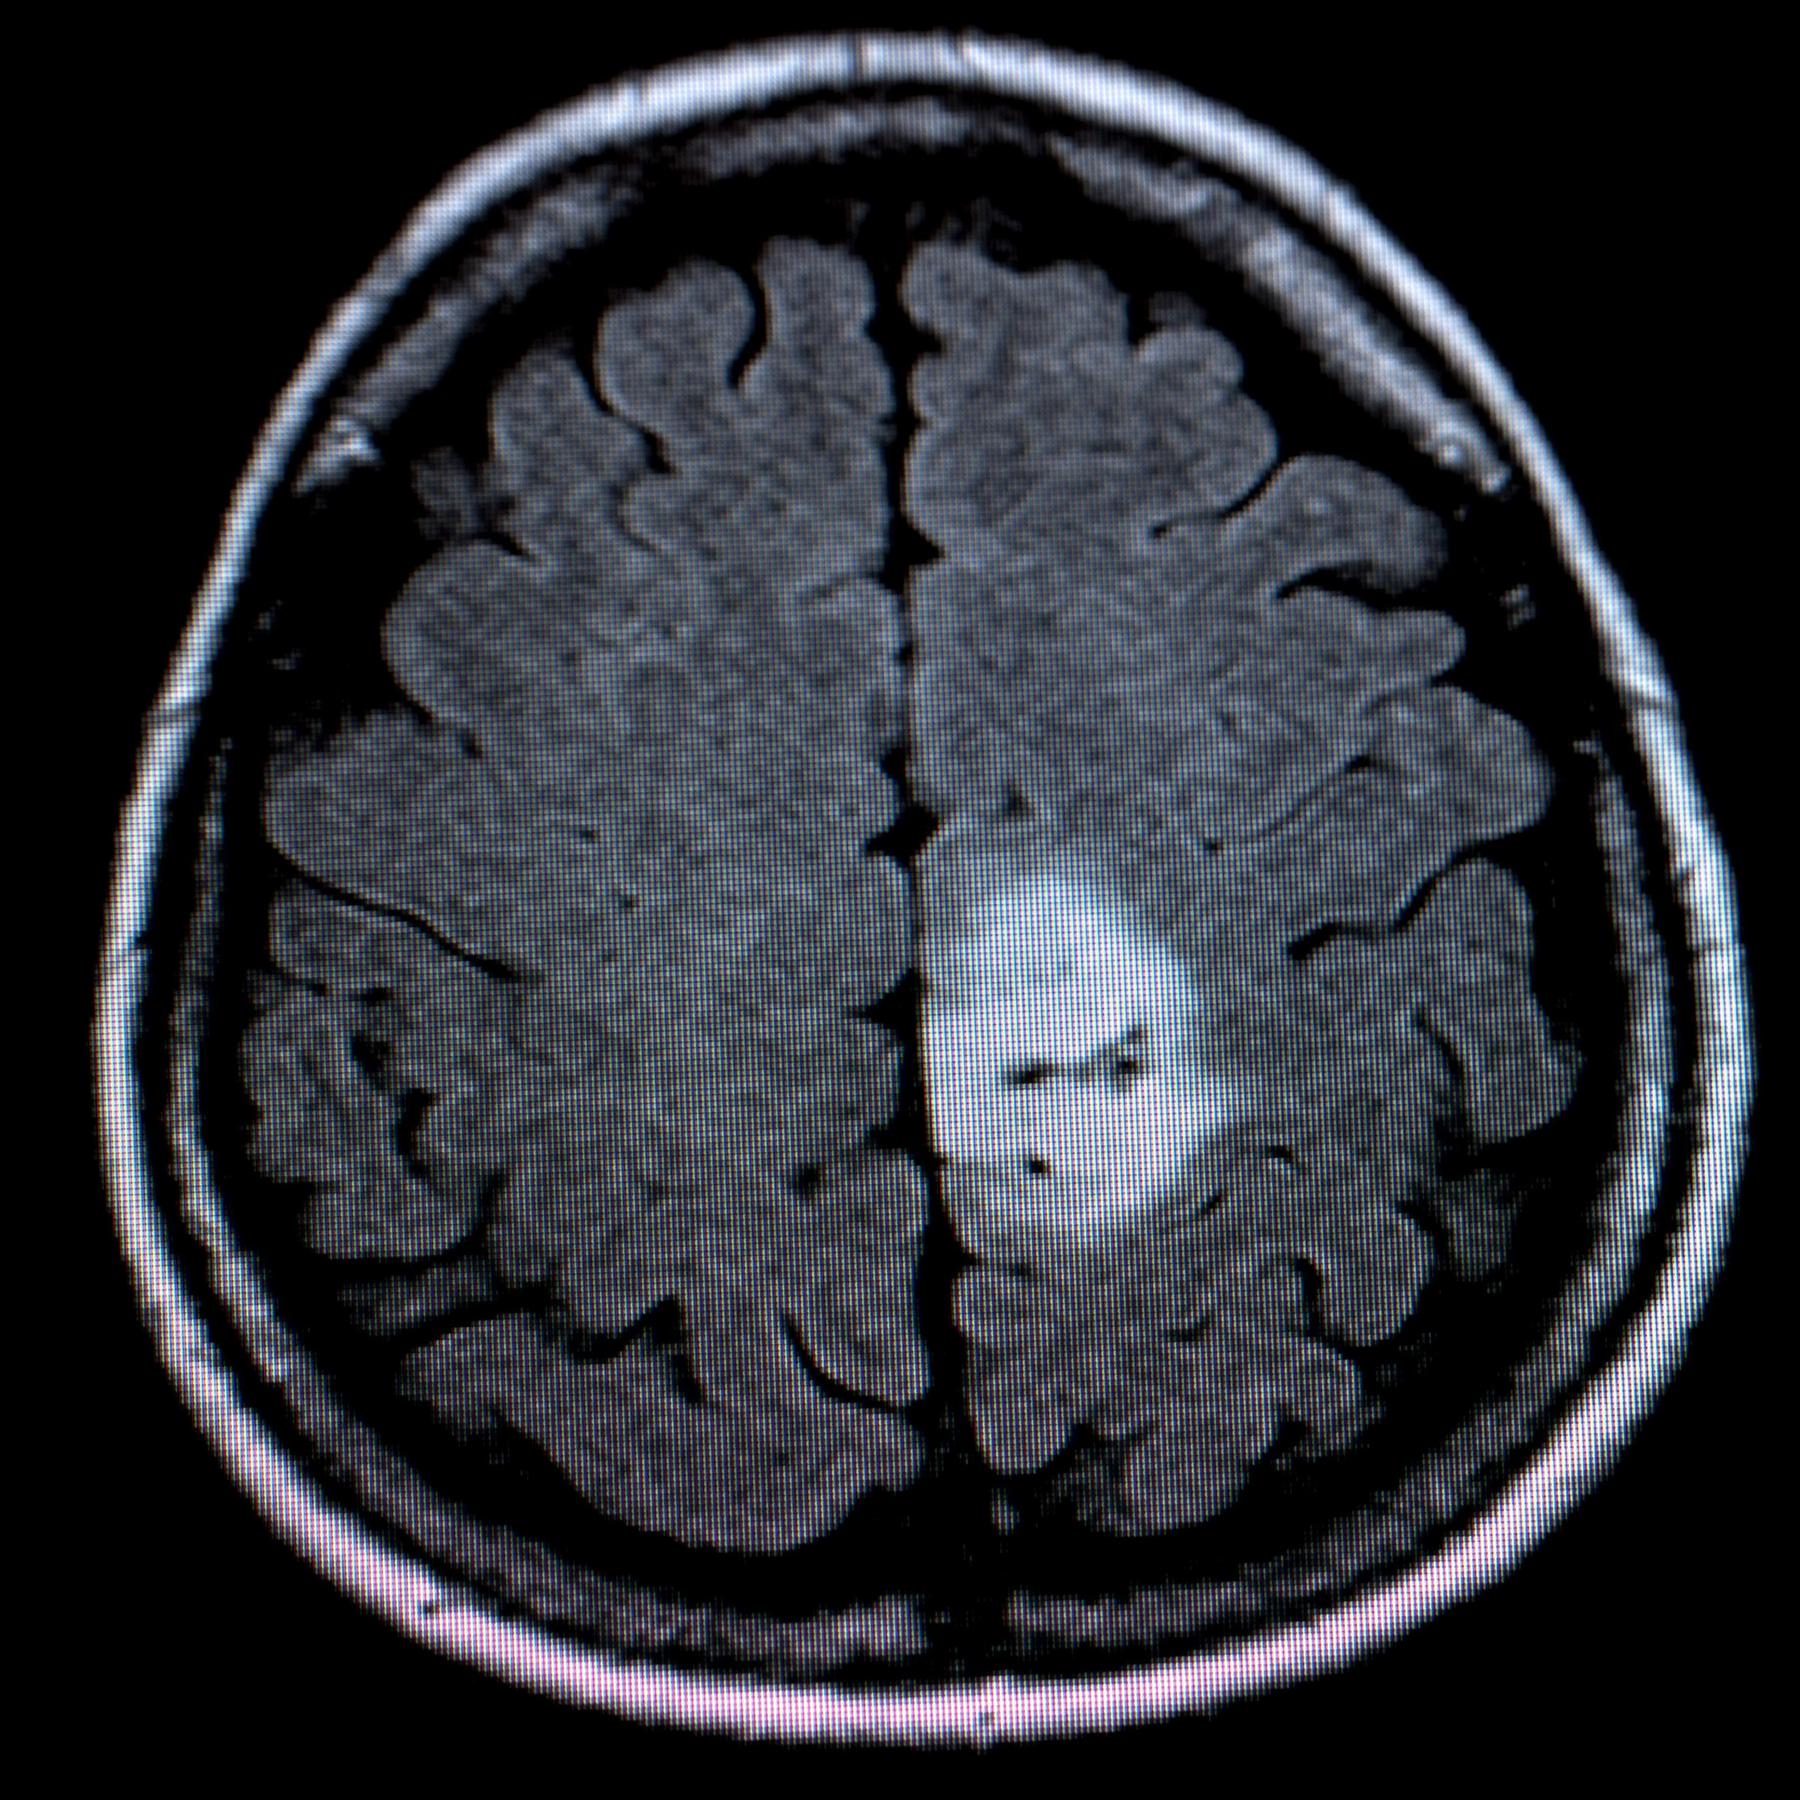

Kopfschmerzen, Sehstörungen oder auch Krampfanfälle - das können Symptome für einen Hirntumor sein - egal, ob gut- oder bösartig. Wie die Medizin inzwischen helfen kann, erklärt der Neurochirurg Prof. Florian Ringel.